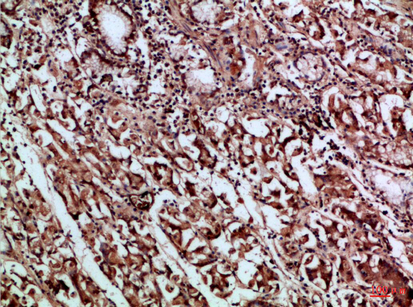

Immunohistochemical analysis of paraffin-embedded Human tonsils using CD66a/b/c antibody.High-pressure and temperature Sodium Citrate pH 6.0 was used for antigen retrieval. |